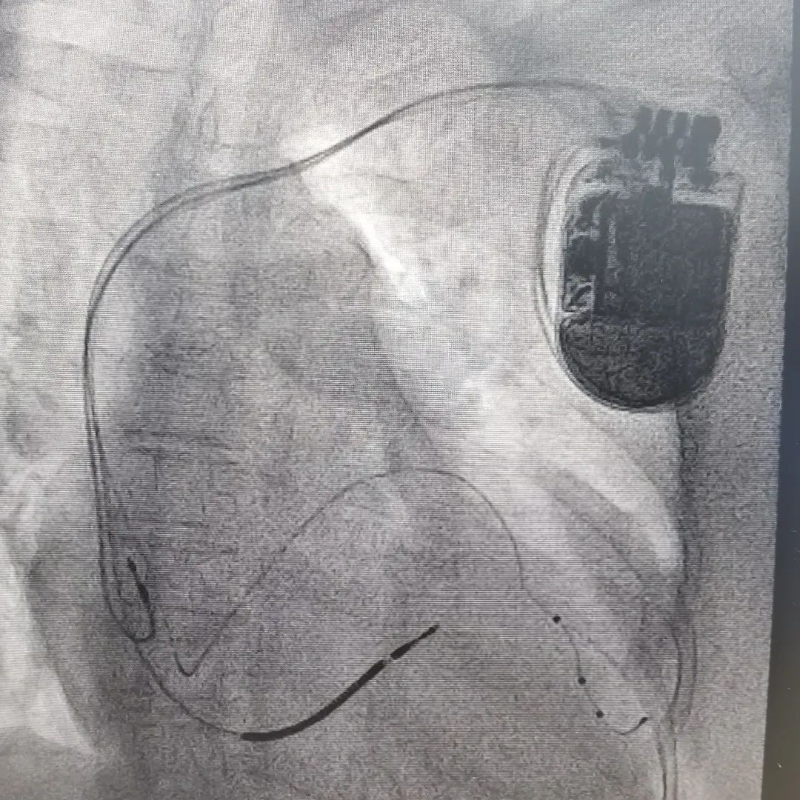

博羅首例!讓心衰患者重獲“心”生——我院心血管內科完成心臟再同步治療心律轉復除顫器(CRTD)植入術

近日,我院心血管內科團隊由謝桂庭主任主刀,為一名“擴張型心肌病、心力衰竭”的患者成功完成心臟再同步治療心律轉復除顫器(CRTD)植入術,有效改善了患者的臨床癥狀。該手術為博羅地區首例,其技術在同級別醫院處于領先地位。

CRTD是心臟再同步化治療合并有除顫功能的起搏器的英文縮寫,相當于把“心臟保鏢”置入心臟里面,一旦患者出現惡性心律失常,CRTD可即刻發現并自動除顫,使患者恢復自正常心跳,達到防止猝死的目的;同時可以幫助心衰患者實現左右心室同步收縮,改善心功能,甚至可以讓擴大的心臟回縮,主要用于各類型心肌病導致的心力衰竭患者。

67歲的朱阿姨在2016年就診斷為“擴張型心肌病”,反復出現氣促、乏力、胸悶等癥狀,多次在我院住院治療。近期,朱阿姨心衰癥狀明顯加重,休息狀態下仍氣促感明顯,夜間睡覺不能平臥,需端坐位入睡,朱阿姨被病魔折磨得度日如年。既往也曾于我院住院期間多次建議植入CRTD治療,但患者及家屬終因各種原因未同意。此次患者心衰癥狀較前明顯加重,只能再次辦理住院,入院復查心臟超聲檢查顯示朱阿姨的心臟明顯擴大,左心室舒張徑達到77mm,射血分數(EF)僅26%;心電圖提示竇性心律,完全性左束支傳導阻滯,QRS波時限達到200ms。心血管內科謝桂庭主任帶領介入團隊討論后認為,各項檢查均提示朱阿姨病情有明顯惡化情況,如果不積極處理,等待朱阿姨的結果就是心力衰竭進行性加重至死亡,或者毫無征兆的猝死。患者有明確CRTD植入術指征,而且因目前CRTD納入國家集采目錄,手術總費用較前大幅下降。取得朱阿姨及家屬同意后,決定為患者實施CRTD植入術,以進一步改善患者的心功能,預防繼發惡性心律失常導致的心臟性猝死。

3月10日,謝桂庭主任帶領介入團隊歷時2小時余成功為患者植入CRTD。

成功植入CRTD后,朱阿姨的心衰癥狀較前改善了,術后復查心電圖,QRS波形寬度由200ms 降為140ms,提示心臟同步收縮功能得到明顯改善,住院期間未再發作惡性心律失常,術后患者切口愈合良好,于術后第三天出院回家休養。

CRTD植入術的成功開展,標志著我院心血管內科在心力衰竭的器械治療和惡性心律失常猝死預防方向又邁出堅實的一步,也將會造福更多本地區的心衰患者。近年來,我院心血管內科以市中心人民醫院派駐專家謝桂庭主任為學科帶頭人,不斷學習開展新技術,實現了一個又一個零的突破,實實在在地讓博羅百姓大病不出縣,贏得了廣泛的認可。